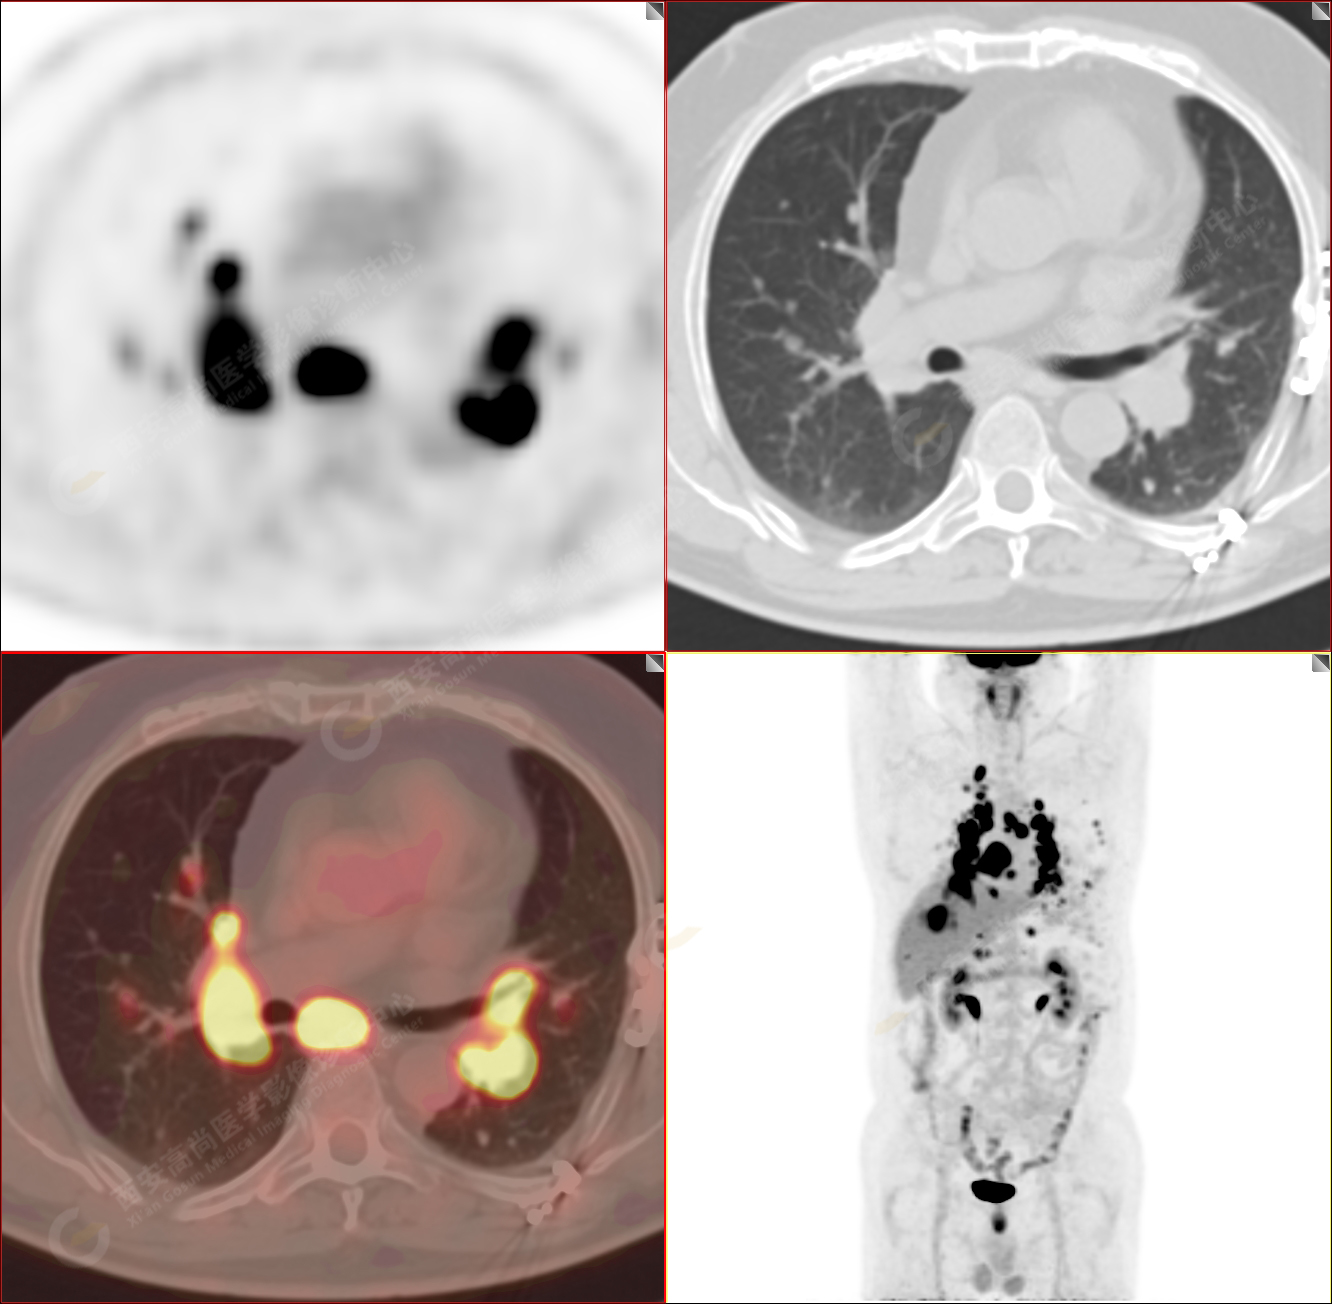

男性,53歲,頭暈半月入院,CT發(fā)現(xiàn)肺內(nèi)腫塊,雙肺多發(fā)大小不等實性及粟粒樣結(jié)節(jié),雙肺門及縱隔多發(fā)腫大淋巴結(jié)。病程中無發(fā)熱、胸悶氣及胸部不適。既往:左側(cè)肋骨外傷史。

PET/CT圖像